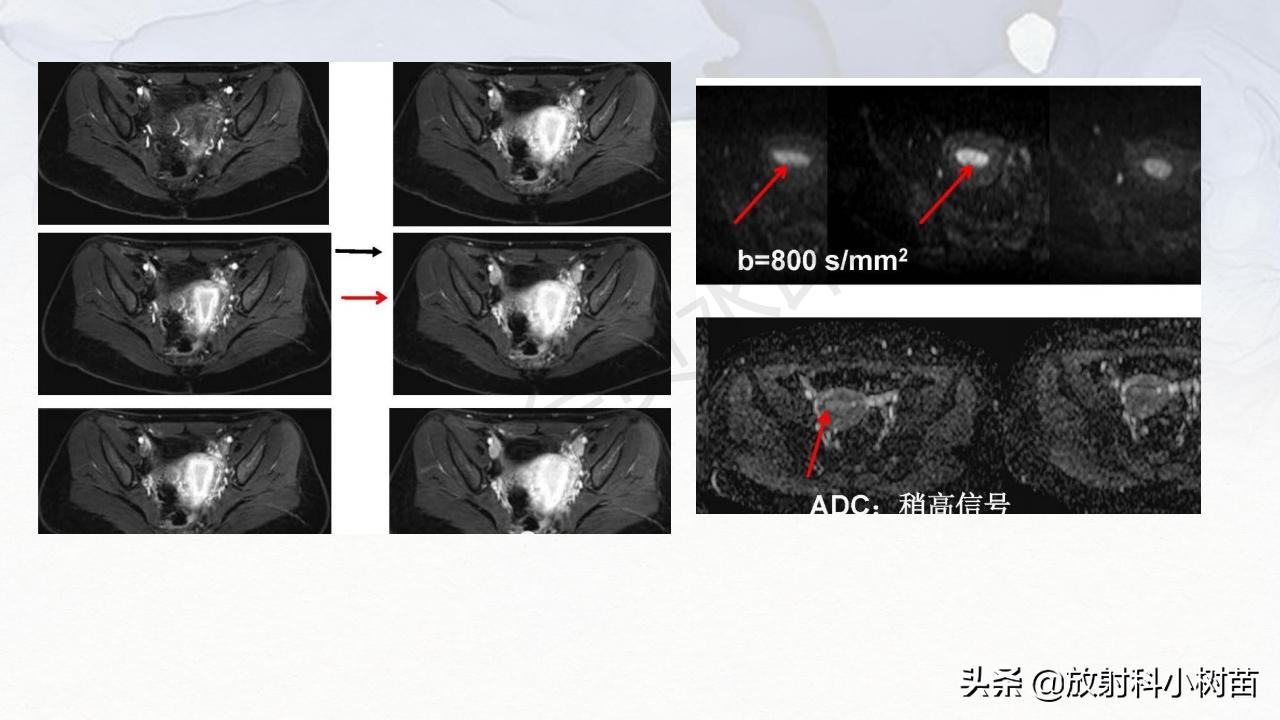

卵巢恶性肿瘤征象:多呈囊实性,实性部分多且强化明显,倾向恶性;

1、肿瘤壁增厚超过3mm

2、肿瘤内分隔增厚超过3m

3、壁内或分隔内出现结节

4、大的实性肿块或伴内部坏死。

5、卵巢癌具有早期转移及向周围侵犯的征象,表现为大量腹水,邻近脏器侵犯,腹膜或网膜种植转移。